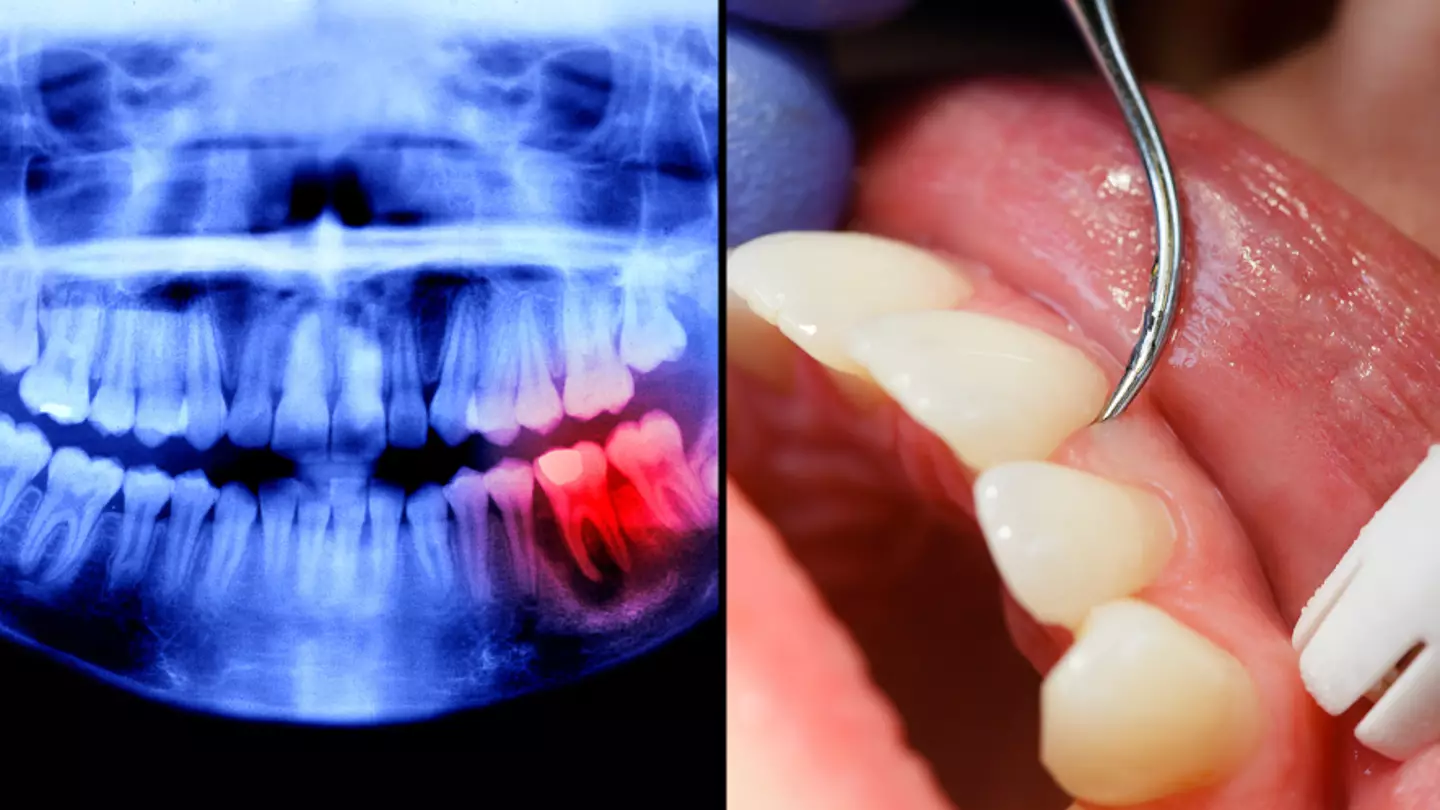

Dr. Chanpreet Kalsi of the Hermes London Dental Clinic said there were warning signs that would be best not ignored, lest you end up with irreversible gum disease.

The first stage of gum disease, known as gingivitis, can be reversed but once it goes beyond that the infection can never be completely removed and you'll be suffering from it forever.

The doc warned that basically half of all adults have non-reversible gum disease, and only 17 percent have perfectly healthy gums.